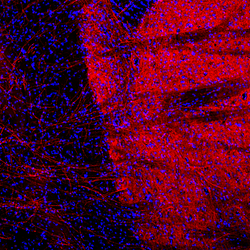

Tyrosine Hydroxylase Monoclonal Antibody for Western Blot, IHC (PFA), ICC/IF

Tyrosine hydroxylase (TH) is an enzyme involved in the synthesis of catecholamine neurotransmitters dopamine, epinephrine, and norepinephrine. In all species, catecholamine synthesis is regulated by the interaction of TH with a cofactor, tetrahydrobiopterin (BH4). BH4 binds to the TH catalytic domain, resulting in enzymatic activity. Unlike TH in non-primate species, four human TH mRNA splice variants (hTH1-hTH4) have been isolated. These variants are identical in their catalytic domain, but differ in their N-terminal, regulatory domains. TH is also responsible for the conversion of L-tyrosine to L-dopa. TH plays a key role in the physiology of adrenergic neurons. The role of TH in the synthesis of catecholamine neurotransmitters suggests a correlation between the enzyme and a number of neuropathogenic diseases including: Parkinson's disease, schizophrenia, Segawa syndrome, and dystonia, as well as a variety of cardiovascular diseases.

Immunohistochemistry (PFA fixed), Western Blot, Immunocytochemistry

Human, Mouse, Rat